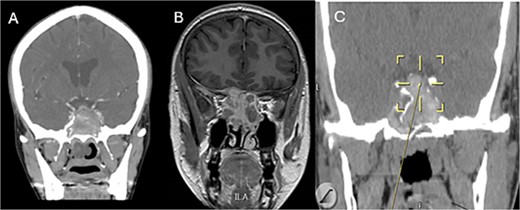

A 69-years-old diabetic female was referred from neurology as she complained of an acute onset severe headache, diplopia, and retro-orbital pressure. An initial CT scan with a subsequent MRI scan (Fig. 5) showed infiltrative sphenoid pathology invading both skull base and cavernous sinus given a provisional diagnosis of acute invasive fungal sinusitis. The patient was urgently taken to the operative theater to endoscopically debride sphenoid sinuses (Fig. 6). Histopathological examination confirmed the diagnosis of invasive sphenoid sinus mucormycosis.

Coronal CT (A) and MRI (B) and CT image guided intra-operative (C) images of the paranasal sinuses showing aggressive sphenoid sinus disease extending to the skull base and cavernous sinus.